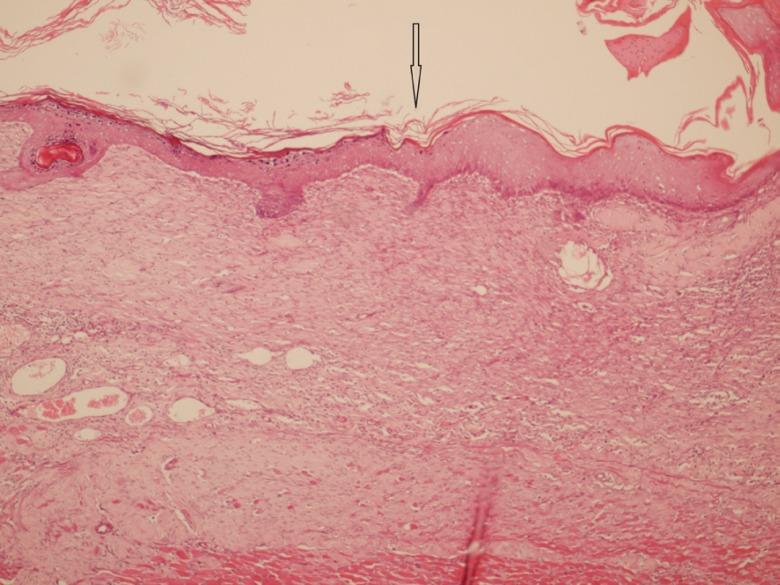

Administration of curcumin resulted into a decrease in size of the burn wounds and a reduction in inflammation after 14(th) days. Reepithelialization was prominent in groups A-C while more distinguishable in group C. In group C, epidermis exhibited well structured layers without any crusting. There were spindle shaped fibroblasts in fascicular pattern, oriented parallel to the epithelial surface with eosinophilic collagen matrix.

给予姜黄素后,14天后烧伤创面大小减小,炎症减轻。A - C组上皮再形成明显,C组更显著。在C组中,表皮呈现结构良好的层次,无结痂。有成束状排列的梭形成纤维细胞,与上皮表面平行排列,伴有嗜酸性胶原基质。